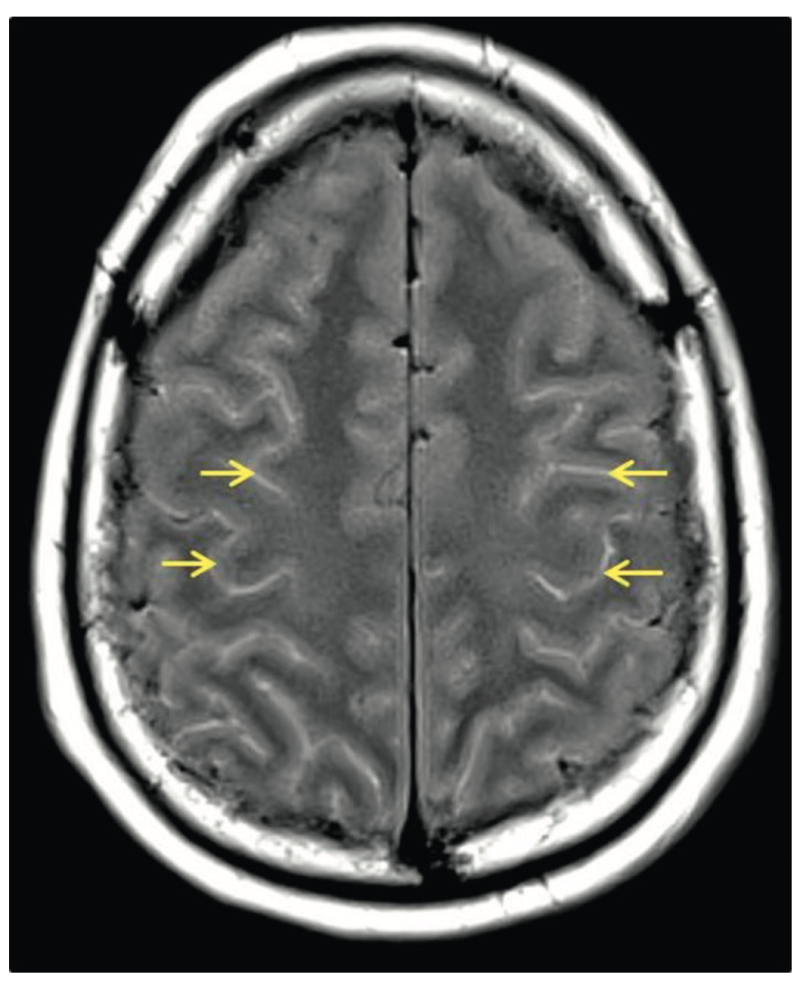

FLAIR: hypersignaux diffus des sillons corticaux